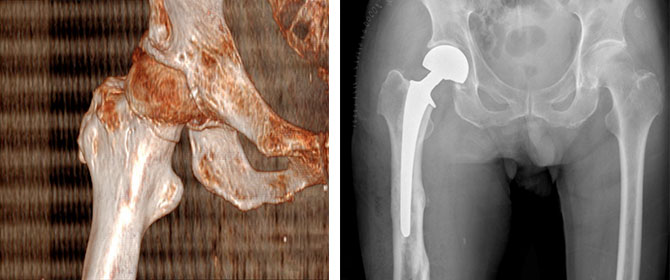

术后老爷爷恢复顺利,复查X线人工股骨头位置良好。依据关节骨病与创伤科近年来大力推进的关节置换术后快速康复流程,在充分评估老人的情况后,在术后第一天开始下地行走锻炼。考虑到老爷爷的近90岁高龄,且无子女身边陪护,医护团队根据老爷爷的情况标注了多处注意事项,制定了个性化的术后锻炼计划,耐心地对老爷爷进行了多次的术后宣教。马元琛主任医师、李曾医师及谢宇医师每天关心老爷爷及老伴的情况,耐心地解答老人的疑问,详细交代术后的注意事项,大大增强了老人康复的信心。老人术后第三天恢复良好,顺利办理了出院。

急诊CT三维重建:右侧股骨颈骨折 人工股骨头置换术后复查片